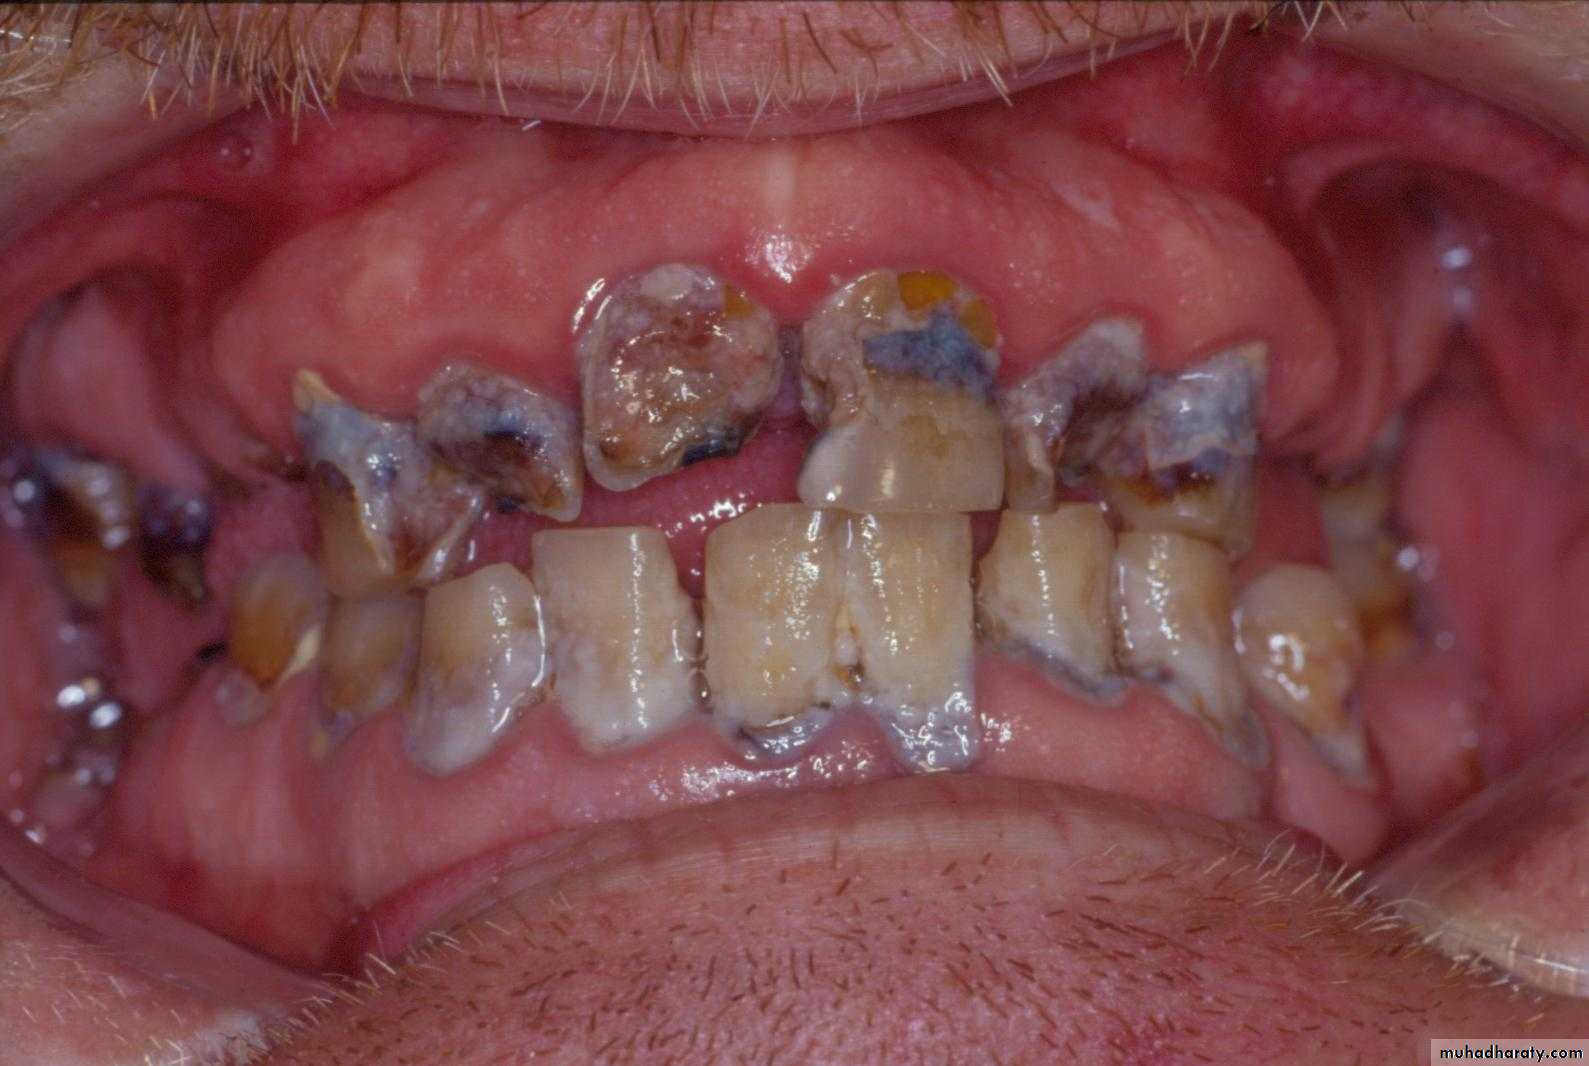

1. Hard tissue2. Soft tissue

1. Hard tissue

a. Dental cariesb. Periodontal disease

c. Infection

a. Extractions for caries, periodontal disease, infection, etc.

a. Extractions…flap, bone removal, section